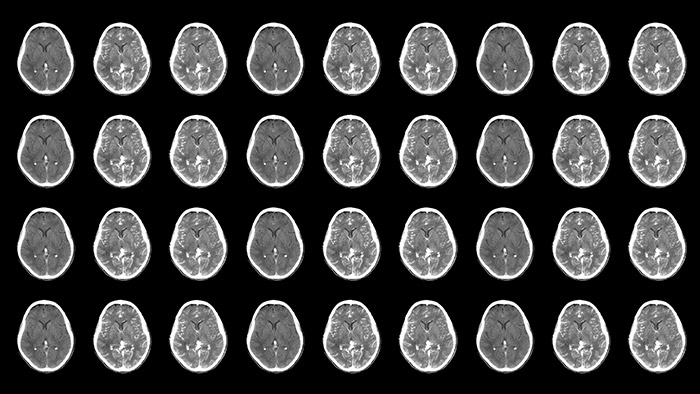

Neurovascular care encompasses a remarkable range in approaches to treatment. On one hand, stroke cases are acute and always require immediate treatment for the greatest chance of improving the patient’s quality of life. On the other hand, planned procedures such as complex treatments for aneurysms and arteriovenous malformations (AVMs) need to be meticulously designed and executed to minimize the inherent risk. Neuro suite with SmartCT makes advanced 3D imaging accessible, offering superior workflow with excellent image quality at low dose. Innovative stroke tools, thoughtful collaboration with partners and 24/7 support help you deliver superior neurovascular care.

Neuro suite offers a flexible portfolio of sophisticated 3D imaging, integrated imaging, integrated technologies, neuro accessories and valued-added services that puts you on top of things, whether treating an acute stroke patient or working precisely through a complex AVM. This allows you to act with confidence, supported by high levels of procedural efficiency and standardization to help redefine outcomes for your patients and provide a positive workflow experience for staff.

Improved neuro CT-like cone beam CT images (CBCT) to identify ischemic changes in the Angio suite. The advanced protocol with dual-axis acquisition trajectory and improved reconstruction software results in improved image appearance, compared to conventional CBCT acquisition techniques.